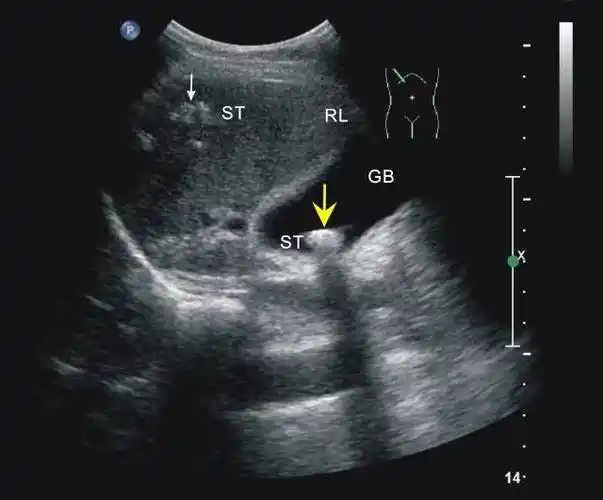

腹部超声不典型胆囊结石泥沙样结石